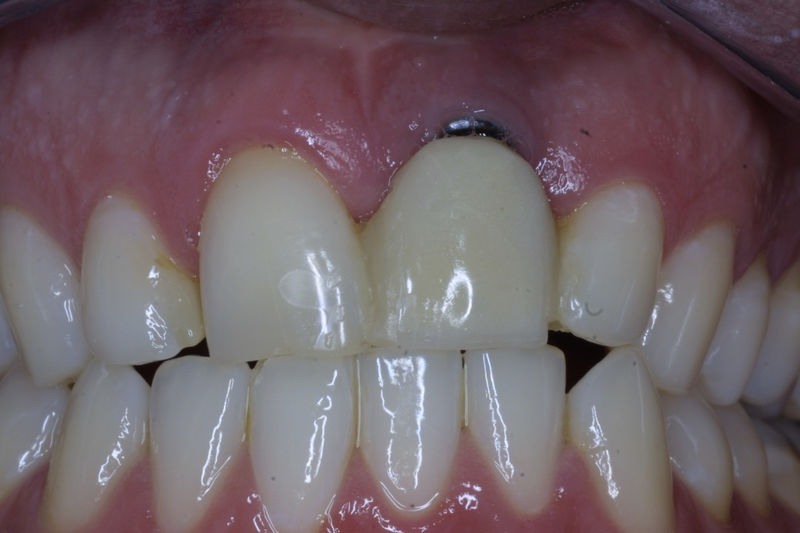

Implante fracasado, extracción, carillas, coronas y prótesis fija.